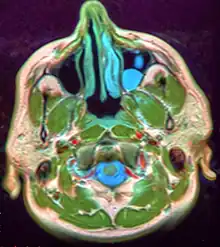

Microscopically, mucoceles appears as granulation tissue surrounding mucin. Since inflammation occurs concurrently, neutrophils and foamy histiocytes usually are present. On a CT scan, a mucocele is fairly homogenous, with an attenuation of about 10-18 Hounsfield units.[5]